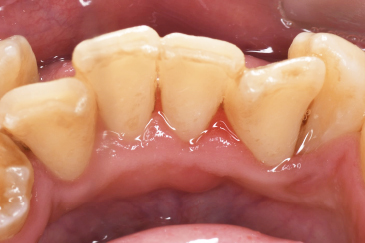

Before①

| 主訴 | 下顎 歯石除去したい |

| 治療内容 | スケーリング |

| 治療期間 | 30分 |

| 治療費 | 約1,500円(保険診療) |

| リスク・副作用 | 知覚過敏、歯肉退縮 |

| 治療方針 | 歯肉縁上歯石を除去してから歯肉縁下歯石を除去します。ご自身でのプラークコントロールができるようになったら定期検診に移行します。 |

| 担当者所見 | 半年ぶりの歯科医院の受診。歯石が付きやすいためセルフケアの重要性をお伝えして、定期的にクリーニングを行います。出血率が高く炎症が強いため、今後はセルフケアを強化して歯周病治療を行います。 |